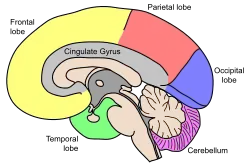

- Córtex cerebral, que inclui: lobo occipital (visão), lobo parietal (órgãos das sensações e cinesia), lobo temporal (audição e olfato próximos ao hipocampo), lobo frontal (julgamento, percepção e zona motora). Os lobos frontal, parietal e temporal são responsáveis pelo aprendizado e todo o córtex é responsável pela linguagem.

O cérebro, que consiste nos hemisférios cerebrais, forma a maior parte do encéfalo e recobre as outras estruturas cerebrais[6] A região externa dos hemisférios, o córtex cerebral, é a massa cinzenta, consistindo de camadas corticais de neurônios. Cada hemisfério é dividido em quatro lobos principais - o lobo frontal, o lobo parietal, o lobo temporal e o lobo occipital.[7] Três outros lobos são incluídos por algumas fontes, que são um lobo central, um lobo límbico e um lobo insular.[8] O lobo central compreende o giro pré-central e o giro pós-central e está incluído, pois forma um papel funcional distinto.[8][9]

O cérebro é a maior parte do encéfalo e é dividido em hemisférios direito e esquerdo quase simétricos por um sulco profundo, a fissura longitudinal.[14] A assimetria entre os lobos é observada como uma petália.[15] Os hemisférios são conectados por cinco comissuras que abrangem a fissura longitudinal, a maior delas é o corpo caloso.[6] Cada hemisfério é convencionalmente dividido em quatro lobos principais; o lobo frontal, o lobo parietal, o lobo temporal e o lobo occipital, nomeados de acordo com os ossos do crânio que os cobrem.[7] Cada lobo ou lóbulo está associado a uma ou duas funções especializadas, embora haja alguma sobreposição funcional entre elas.[16] A superfície do cérebro é dobrada em cristas (giros) e ranhuras (sulcos), muitos dos quais são nomeados geralmente de acordo com sua posição, como o giro frontal do lobo frontal ou o sulco central, que separa as regiões centrais dos hemisférios. Existem muitas pequenas variações nas dobras secundárias e terciárias.[17]

O córtex é mapeado por divisões em cerca de cinquenta áreas funcionais diferentes, conhecidas como áreas de Brodmann, que são nitidamente diferentes quando vistas ao microscópio.[20] O córtex é dividido em duas áreas funcionais principais - um córtex motor e um córtex sensorial.[21] O córtex motor primário, que envia axônios para os neurônios motores no tronco cerebral e na medula espinhal, ocupa a parte posterior do lobo frontal, diretamente na frente da área somatossensorial. As áreas sensoriais primárias recebem sinais dos nervos e tratos sensoriais por meio de núcleos de retransmissão no tálamo. As áreas sensoriais primárias incluem o córtex visual do lobo occipital, o córtex auditivo em partes do lobo temporal e o córtex insular e o córtex somatossensorial no lobo parietal. As partes restantes do córtex são chamadas de áreas de associação, que recebem informações das áreas sensoriais e partes inferiores do cérebro e estão envolvidas nos complexos processos cognitivos de percepção, pensamento e tomada de decisão.[22] As principais funções do lobo frontal são controlar a atenção, o pensamento abstrato, o comportamento, as tarefas de resolução de problemas e as reações físicas e a personalidade.[23][24] O lobo occipital é o menor lobo; suas principais funções são recepção visual, processamento visual-espacial, movimento e reconhecimento de cores.[23][24] Existe um lóbulo occipital menor no lobo conhecido como cúneo. O lobo temporal controla as memórias auditivas e visuais, a linguagem e um pouco da audição e da fala.[23]